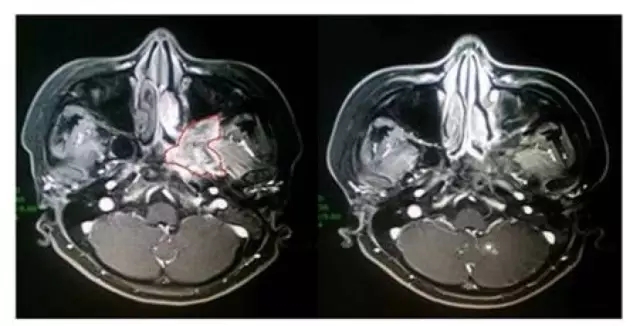

(左側為接受治療前影像,紅色框內為病灶,右側影像為治療后。)

這是一名34歲的女性腺樣囊性癌患者,于2015年4月,MRI結果顯示患者左側翼腭窩占位,并廣泛累及周圍結構,手術難度較大。在2015年7月-8月期間,接受過質子重離子根治性治療后,腫瘤就較前縮小;接受治療6個月后復查顯示,腫瘤病灶已完全退縮。患者目前仍在隨訪階段,尚未發現腫瘤復發或轉移。治療期間,患者僅出現輕微口干的癥狀。目前,患者已治療后已達9個月,一般情況良好。

這個案例幾乎彰顯了質子重離子治療技術的全部優勢:對手術難度高、靠近重要器官的腫瘤能夠進行治療,且治療效果較好,相比傳統放療,患者承受的毒副作用更小。